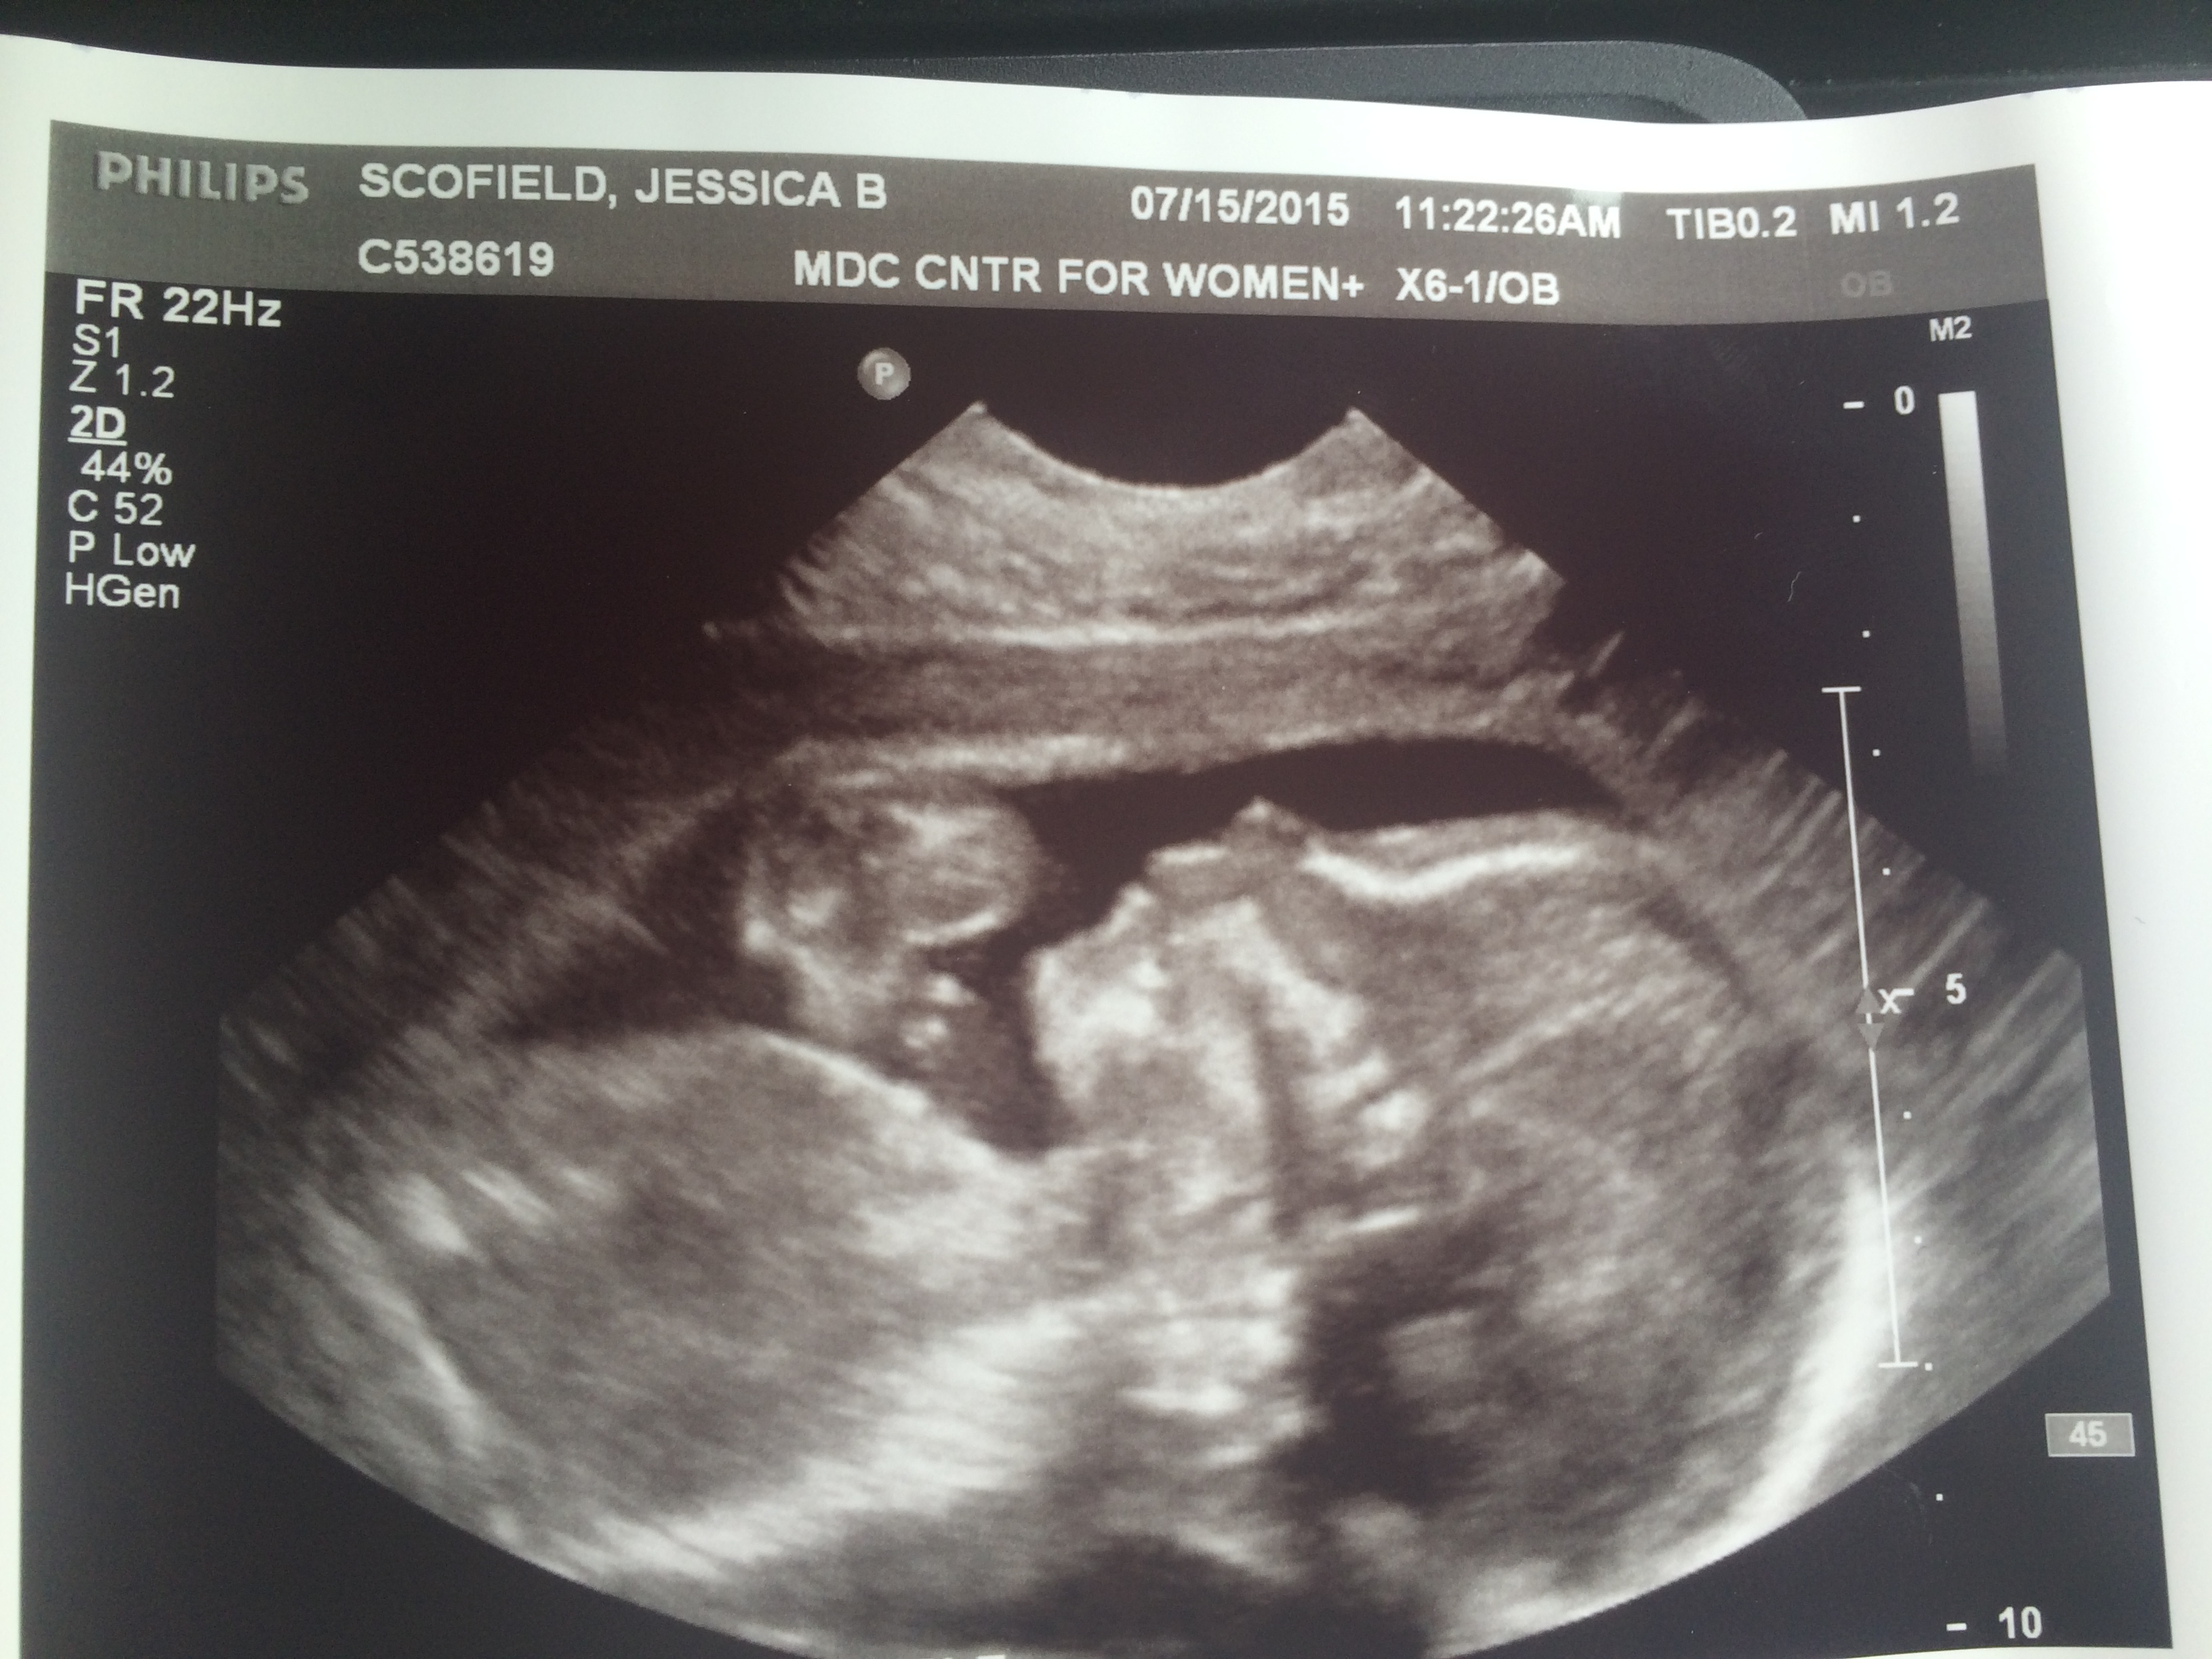

I had a rough week of pregnancy last week. And by rough, I’m not saying anything other than I was just ridiculously uncomfortable, sleepless, full of heartburn and reflux and backaches and all around moderately suffering to grow this baby who’s been continuously punching my bladder for months now. And it’s a good thing, to feel him or her move around in there so vigorously, reminding me that all is well and I am grateful for that. But I’m also, you know, pretty damn uncomfortable. So I’ve been whining about it to my husband, which I don’t take for granted. It’s a gift to us to be able to whine about the little inconveniences of creating a miracle and a dream come true.

I have about one month to go in this second pregnancy. This week I have one more trip to take across the state to talk with students in a few schools about poetry and writing, and I’m looking forward to it. And then it’s home to hunker down, wrap up some work and follow my husband around and annoy him about moving furniture, and boxes and desks and getting things ready for our new tiny roommate.

I can’t wait to meet him. Have I shared that my guess is it’s a boy?

Which probably means it’s a girl.

I woke up this morning to the baby in my belly kicking, rolling and stretching his or her arms, snapping me instantly out of a dream and into the reality of another day spent being a pregnant mother.